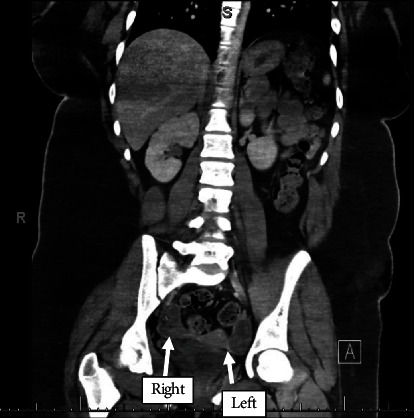

Background: Anti-NMDA receptor (A-NMDAR) encephalitis is an autoimmune condition often associated with ovarian teratoma. Surgical removal of the teratoma is generally curative, and recurrence is uncommon. Case: A 14-year-old female presented with psychiatric symptoms and was ultimately diagnosed with A-NMDAR encephalitis during a prolonged hospitalization. She was found to have bilateral ovarian teratomas, underwent laparoscopic bilateral ovarian cystectomy, and returned to neurologic baseline within 2 months. One year later, the patient was re-presented with similar symptoms and was diagnosed with recurrent A-NMDAR encephalitis. Initial imaging was negative for ovarian teratomas. After another prolonged hospitalization, repeat imaging ultimately demonstrated a suspected left ovarian teratoma. A left salpingo-oophorectomy was performed, and the patient's condition again fully recovered. Conclusion: This case of A-NMDAR encephalitis presented with many atypical features including neuropsychiatric presenting symptoms, bilateral teratomas, and severe recurrence of disease. While imaging is the recommended modality for investigation of etiology, no teratoma was identified on the second presentation, leading to an ethical and clinical conundrum in this adolescent patient. More research is needed to investigate other diagnostic methods for A-NMDAR encephalitis without distinct teratoma on imaging in female patients.

Abstract Image